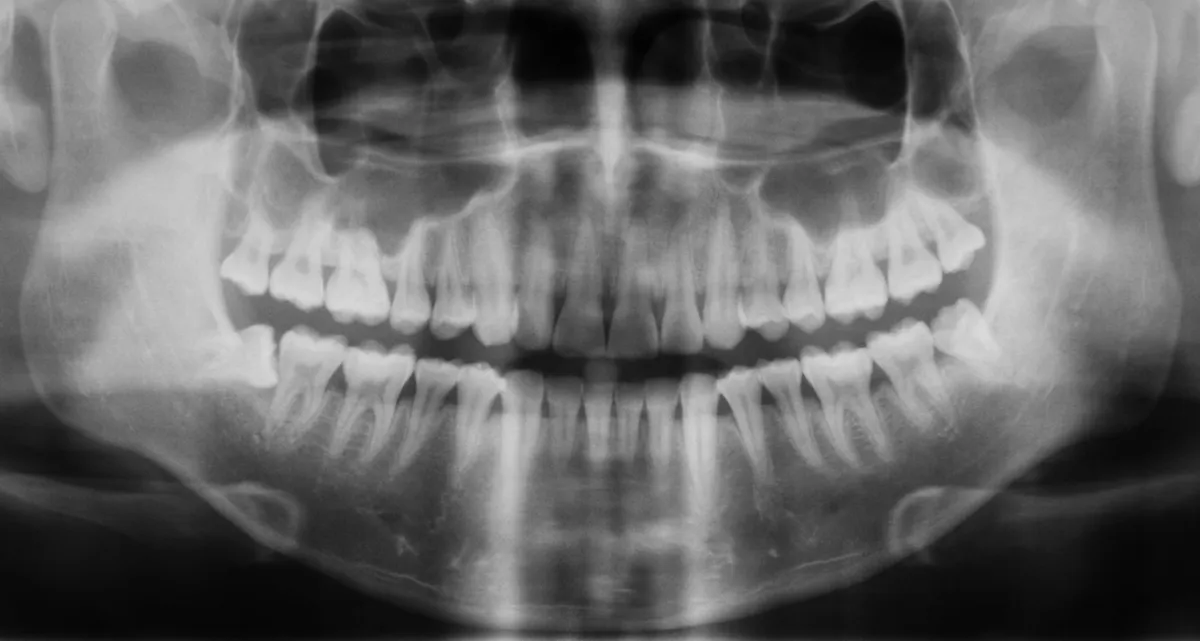

„A múlt héten egy egyszerű gyökérkezelésre számítottam, de a fogorvos a panorámaröntgen elkészítése után közölte, hogy a felvételen egy olyan kiterjedt gyulladás látható, hogy az őrlőfog már menthetetlen, mi több, veszélyezteti az épeket is. Nem volt sok időm gondolkodni, és az orvos szakértelmében bízva elfogadtam a javaslatát, így beleegyeztem a húzásba” – mondta a lapnak Sándor, aki kapott két érzéstelenítő injekciót, majd kiküldték várakozni, amíg a szer kifejti hatását. Miután egy másik pácienst elláttak, az asszisztens szólt a férfinak, hogy visszamehet. A beteg tehát ismét beült a fogorvosi székbe, nagyra tátotta a száját, majd a doktornő egy fogóval feszegetni kezdte a beteg fogat, ami a vártnál nehezebben lazult. A beavatkozás már bő húsz perce tartott, amikor az orvos egy határozottabb rántással megpróbálta a fogat eltávolítani.